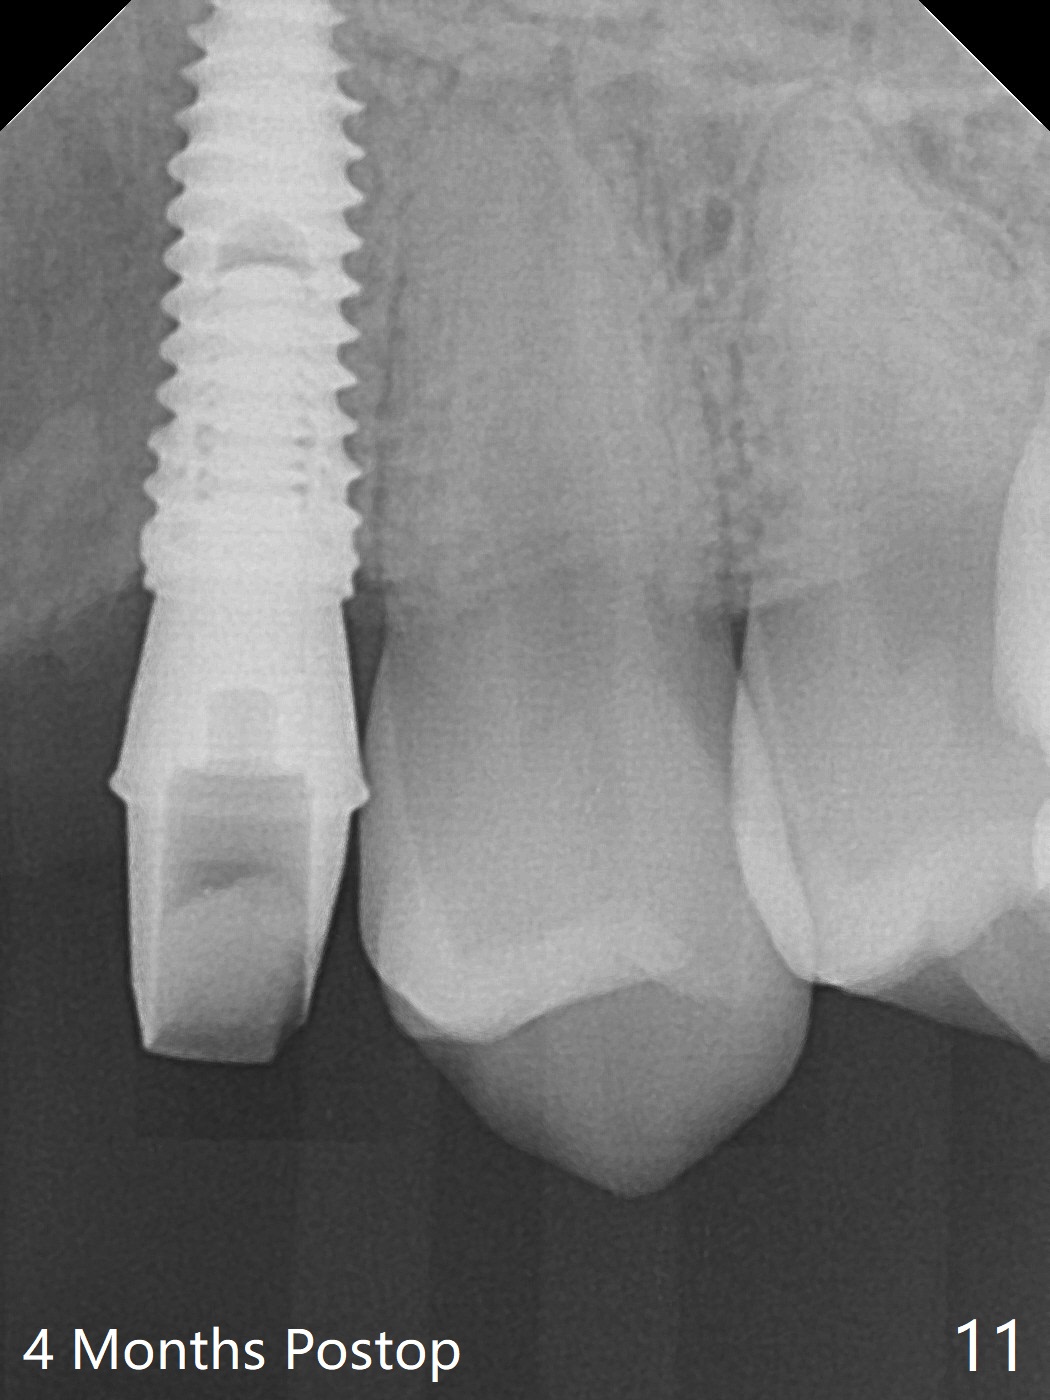

18岁男,本月底到外州上大学,急于十九岁前完成治疗,保险可以多付些。术前检查显示双侧尖牙(图一,二 6,11)根尖,侧切牙牙槽嵴萎缩(*),尖牙、侧切牙之间颊侧做垂直切口,骨膜下潜行分离,在尖牙根尖隧道植骨,然后使用导板,植入窄植体(图四至六),接近或者穿过上颌窦底板(图三,四箭头),骨粉(粘性骨块做的不成功,图五,六 *)好像覆盖暴露的螺纹。再次补充隧道骨粉后,放置修复基台(图七,八),调整后(图九),取模做临时悬臂桥,临床上有些困难分配尖牙,侧切牙比例。术后4个月左侧植体愈合正常(图十,十一),而右侧感染。